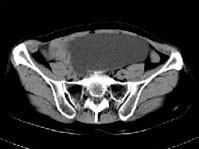

女, 62 岁, 左下腹持续性疼痛 3 天, 伴恶心、呕吐, 左侧附件区扪及一囊性包块, 活动, 表面光滑, 压痛明显,CT和MRI检查如图所示,下列说法...

问题 女, 62 岁, 左下腹持续性疼痛 3 天, 伴恶心、呕吐, 左侧附件区扪及一囊性包块, 活动, 表面光滑, 压痛明显,CT和MRI检查如图所示,下列说法错误的是 ( )

选项 A、结合临床症状,考虑为卵巢囊肿扭转 B、结合临床症状,考虑为卵巢囊腺瘤 C、该病灶包膜完整,边界清晰 D、膀胱向下压移位 E、左侧附件区一囊性占位性病变

答案 B